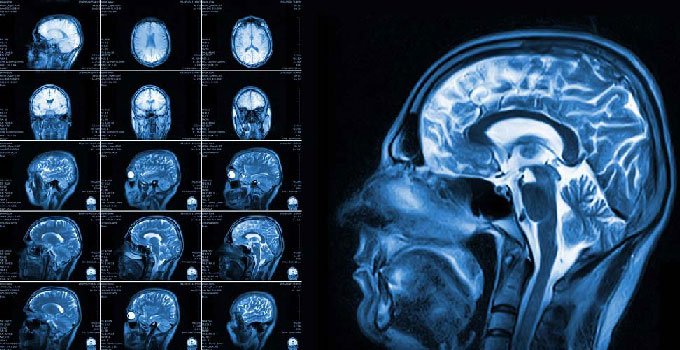

Магнітно-резонансна томографія (МРТ) — ця штука виглядає як наукова фантастика. Потужні магніти, без променевого навантаження, ультраточна візуалізація внутрішніх органів. Це — чарівний метод вивчення людського тіла. Але, на відміну від рентгену чи КТ, тут є одна важлива штука: метал.